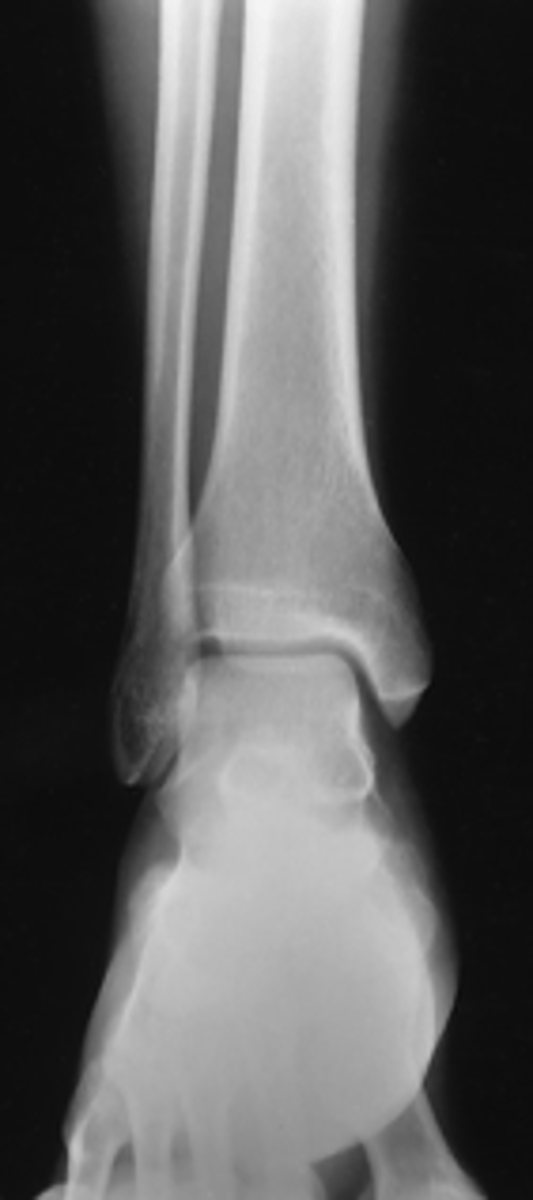

AP Ankle

What projection is this?

Evaluation Criteria AP Ankle

- AP

- CR midway between malleoli

- Distal ⅓ of tibia and fibula demonstrated

- Proximal ½ of metatarsals included

- Medial and superior aspect of ankle joint open